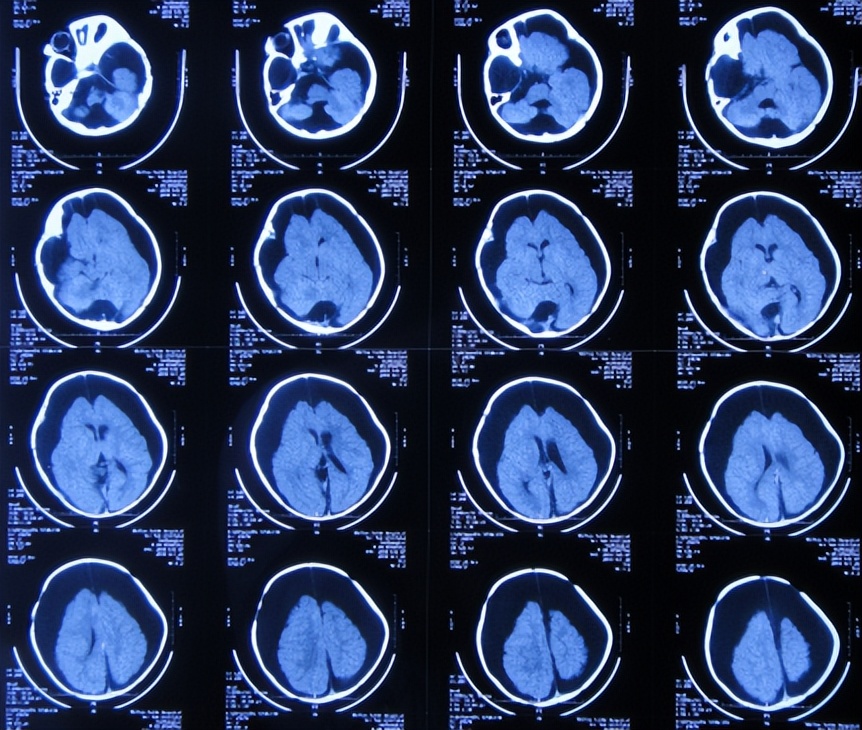

2019年3月22日(蛛网膜囊肿术后近6个月持续硬膜下积液:外院4家医院先后4次手术均失败,且加重脑积水颅内感染,间断发热12天),入院时:头围52cm,体温高热38.5度,浅昏迷,前卤门触摸坚硬,皮肤苍白,四肢刺痛后能动,不能哭,半个身体不能动,头上多处手术疤痕( 图-22 );入院时头颅影像示蛛网膜囊肿术后,硬膜下积液腹腔分流术后,脑积水( 图-23 );右肺肺炎(片子丢失)。

图-23: 2019年3月22日入院时头颅影像